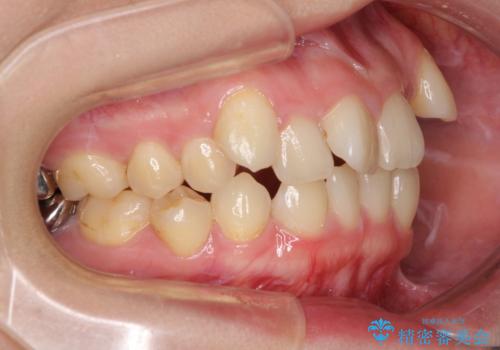

上顎の八重歯と下顎前歯の欠損 ワイヤー装置による抜歯矯正

診察したところ、下顎前歯が2本欠損していたため、上下のバランスを取りながら八重歯を改善するため、上顎左右第一小臼歯2本を抜歯することとしました。

下顎左右大臼歯の歯根部に病変があったため、矯正治療前に根管治療を行い、矯正治療後にセラミッククラウンによる補綴治療を行うこととしました。

下顎前歯と本来抜歯矯正で抜歯する歯とは大きさが異なるため、仕上がりの咬み合わせは理想的なものとはなりませんでしたが、気になっていた八重歯はきれいに改善することができました。